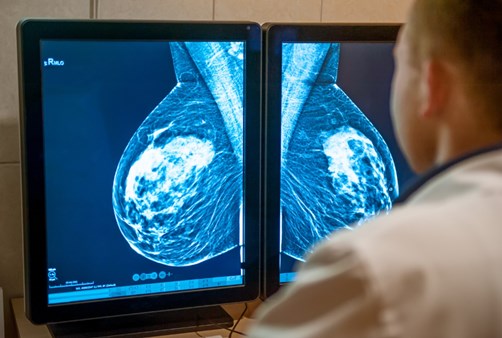

El cáncer es una enfermedad que se caracteriza por ser de difícil diagnóstico en sus primeras etapas, con tumores muy pequeños, cuando son más fáciles de tratar. Precisamente, una de las innovaciones de la Inteligencia Artificial (IA) es el desarrollo del diagnóstico de una forma mucho más rápida y exacta.

Un nuevo estudio, realizado en el año 2021 con más de 80.000 mujeres en Suecia, publicado en la prestigiosa revista The Lancet Oncology, reveló que el cribado con esta tecnología tiene mayor capacidad de detección de cánceres de mama. Esto, en comparación con la doble lectura de mamografías con dos radiólogos expertos.

Los resultados indican que en el grupo asistido por IA se detectaron los casos de cáncer con un 20 % más de acierto si se comparan con el estándar normal (244 diagnósticos con IA vs 203) aunque en ambos grupos la tasa de falsos positivos fue similar, del 1.5 %, es decir, en los casos en los que el primer examen sospechó erróneamente de cáncer. Así, en el proceso de cribado con IA solo se necesitaría de un radiólogo, por lo que su uso podría reducir la carga de trabajo, tiempo y dinero a la mitad de lo que utilizamos ahora.

Al respecto, el Dr. Mauricio León Rivera, director de la Liga Contra el Cáncer, director médico del Centro Detector del Cáncer y cirujano oncólogo de la Clínica Ricardo Palma, expresó que el diagnóstico por imágenes con IA apunta sobre todo a distinguir «lo normal de lo anormal» permitiendo filtrar rápidamente las imágenes de tal manera que los radiólogos concentren su juicio en los casos más complejos.